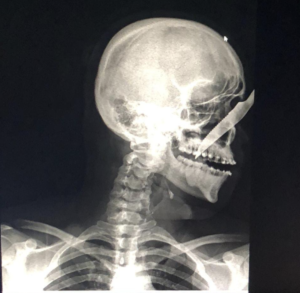

Homem fica com faca cravada no rosto após ataque no interior do Amazonas

Amazonas – O jovem Alberto Carvalho de Oliveira, de 25 anos, ficou com uma faca cravada no nariz após ser atacado por André Luís Benevides Carvalho, 35, na última sexta-feira (17), em Carauari.

Alberto sobreviveu com a faca cravada no rosto e foi socorrido e encaminhado para o hospital do município onde passou por procedimento cirúrgico e André foi levado para a delegacia pela Polícia Militar.